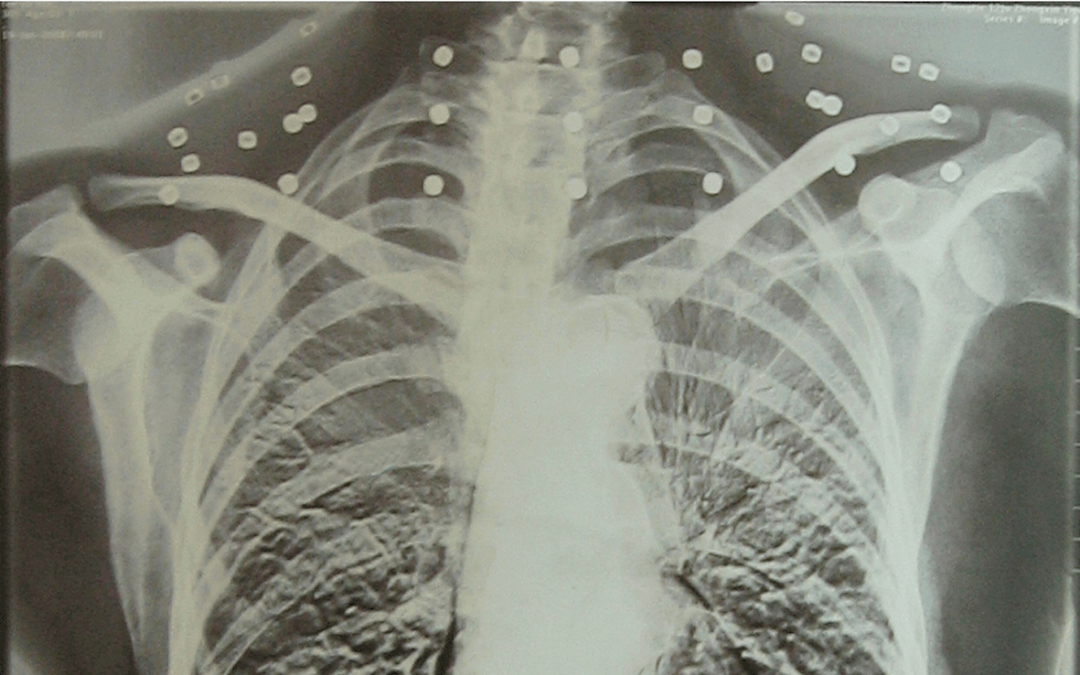

这张照片

是今年82岁的吴以先老人

拍摄的一张CT照

吴以先的颈部和腹部

共分布着33枚弹片

皇冠登一登二登三区别他体内的弹片都没有取出

身体留有弹片的位置就有痛感

但吴以先不考虑取出弹片

在皇冠登一登二登三区别他看来

这是皇冠登一登二登三区别他与战友并肩作战的见证

是皇冠登一登二登三区别他的勋章

与吴以先身上那33枚弹片

一起永远烙印在皇冠登一登二登三区别他心中

33枚“军功章”

是一名军人的光荣